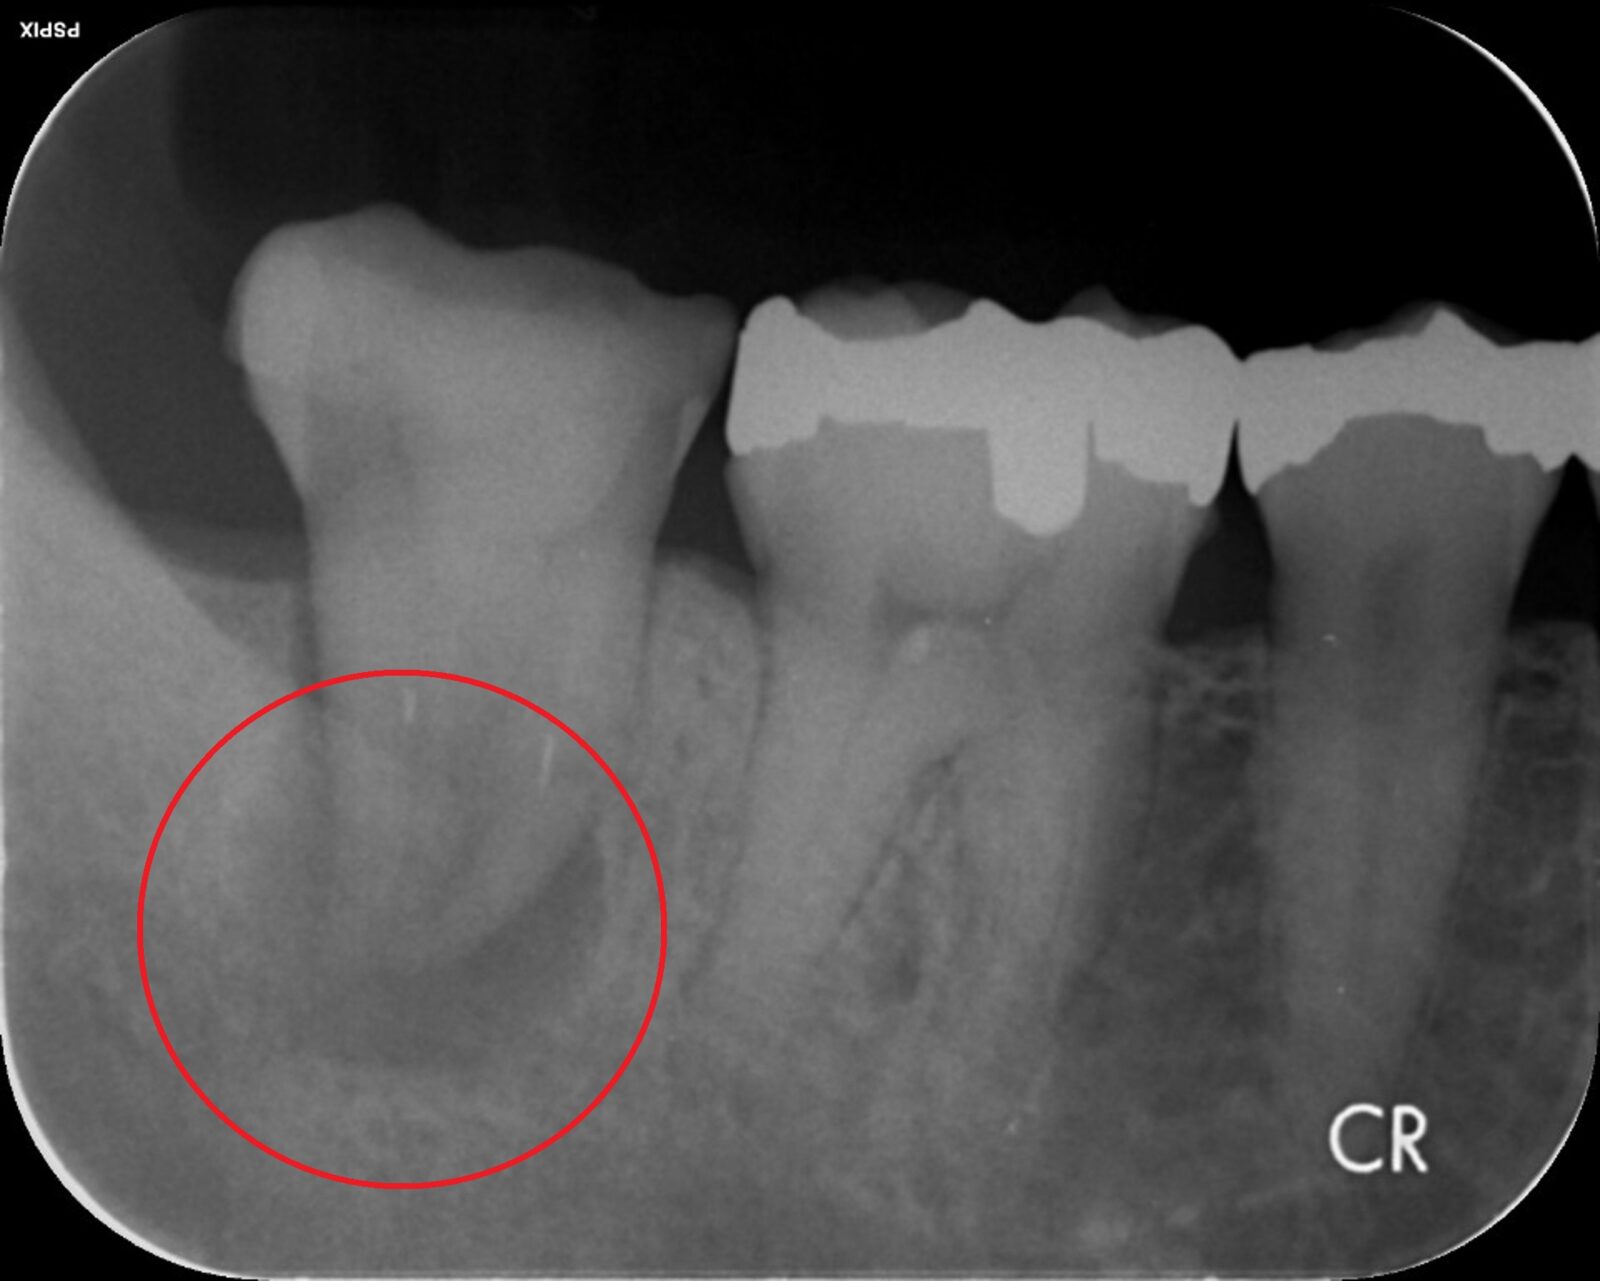

歯の根の「先端」に膿が溜まる状況を「根尖病巣」と言います。これも「抜歯宣告」される代表例です。このケースでも「歯根端切除術」という術式で、抜歯せずに治療できる場合があります。歯根端切除術では、歯茎の外側を切り開き、歯の根の先端ごと膿の袋を取り除きます。取り除いた後の空洞は血液で満たされ、時間の経過とともに骨が再生していきます。